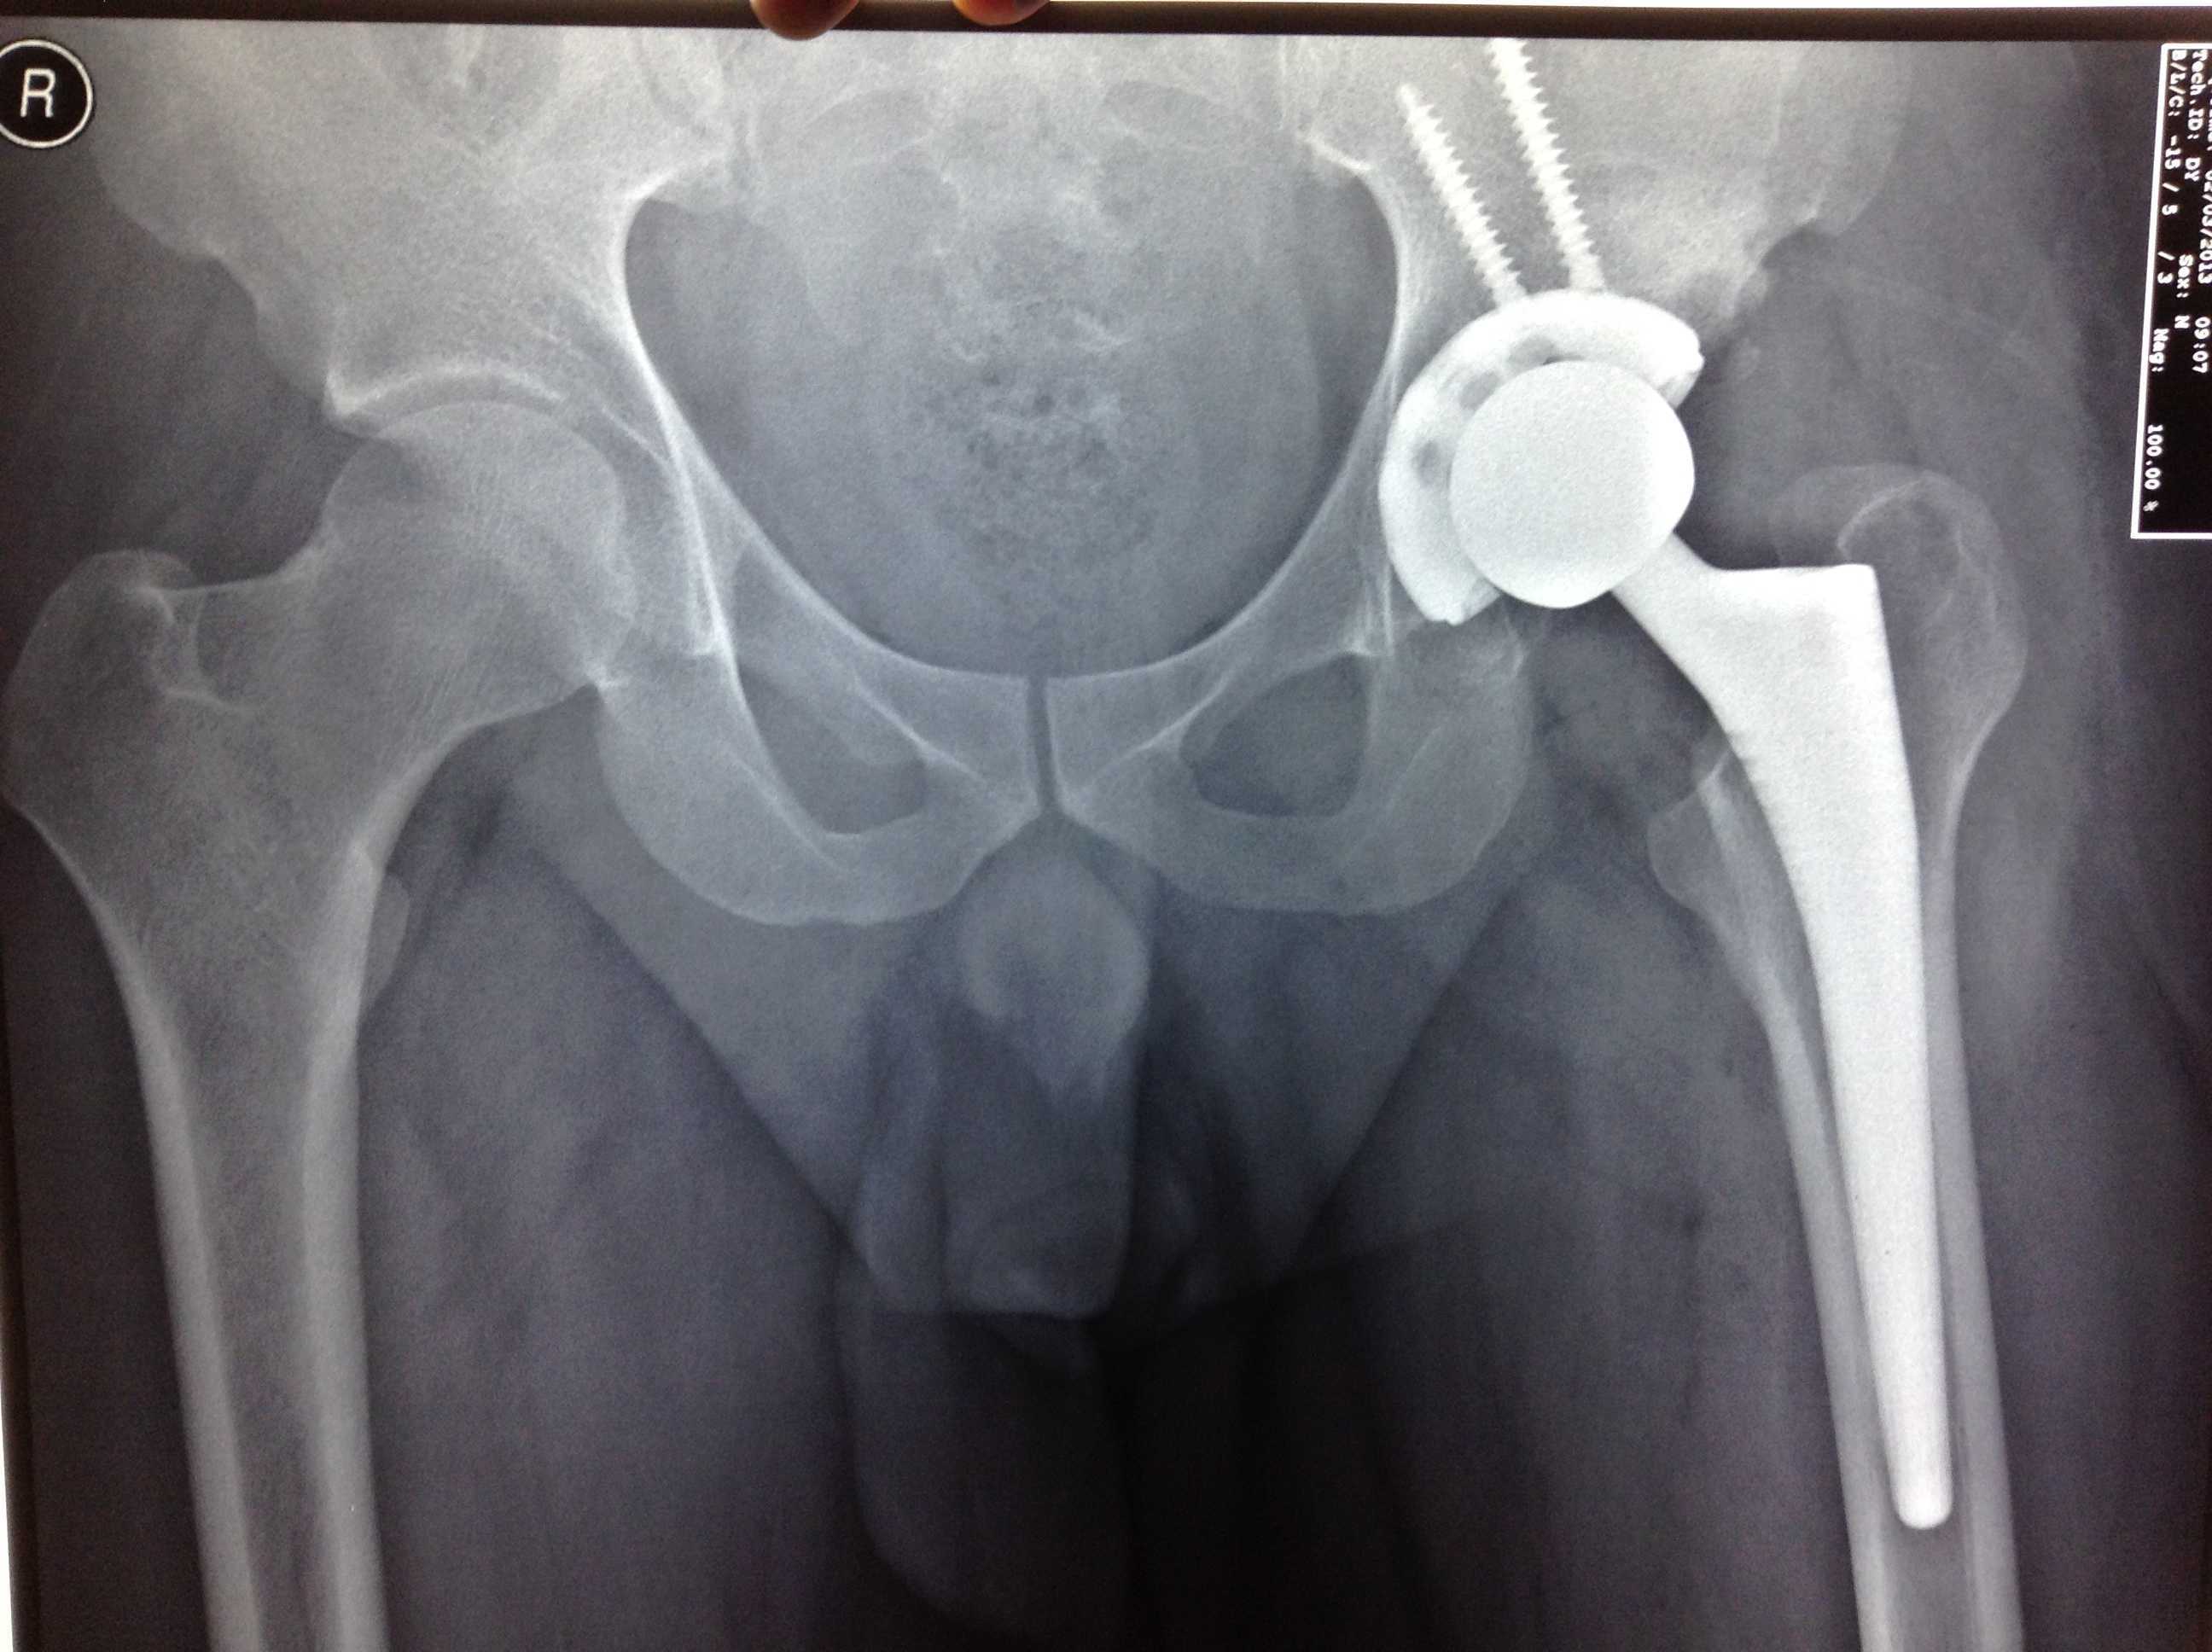

high hip dislocation

• high hip dislocation